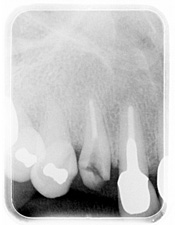

【2】

レントゲンで、過剰歯(余分にできた歯)の存在が分かります。

過剰歯の影響で右上1番目の永久歯が90度捻転しているのが確認できます。

2年後のレントゲンです。

右上の乳歯は自然脱落しています。

その下の永久歯は90度捻転していたものが改善しているのが分かります。